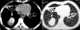

Mucoid impaction in bronchus